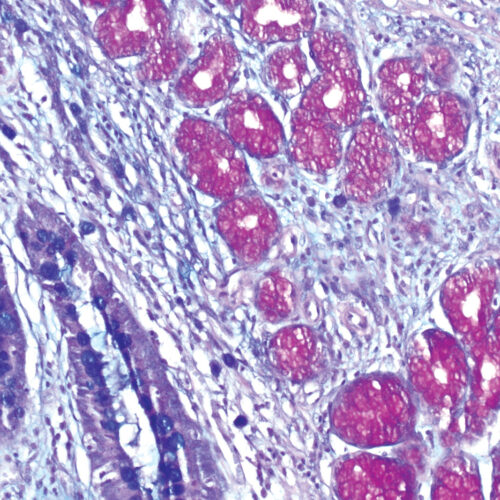

Azan Trichrome kit

Five-reagent kit for connective tissue staining according to Mallory. Used for visualization of muscle fibers, collagen, glial cells, glomerular cells and erythrocytes.